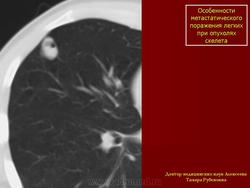

Особенности метастатического поражения легких при опухолях скелета

Для опухолей костей характерен гематогенный путь метастазирования, при котором наиболее часто отмечается изолированное поражение легочной ткани в виде солитарных или множественных очагов и фокусов уплотнения небольших размеров от 0,5см до 1,5-2,5см. Учитывая патологоанатомические варианты остеосарком метастазы в легочной ткани по своим скиологическим признакам напоминают строение первичной опухоли, поэтому структура их неоднородна за счет очажков обызвествлений

Компьютерные томограммы органов грудной клетки: в различных отделах легких округлой и овальной формы образования с четкими контурами, в отдельных видны известковой плотности включения .